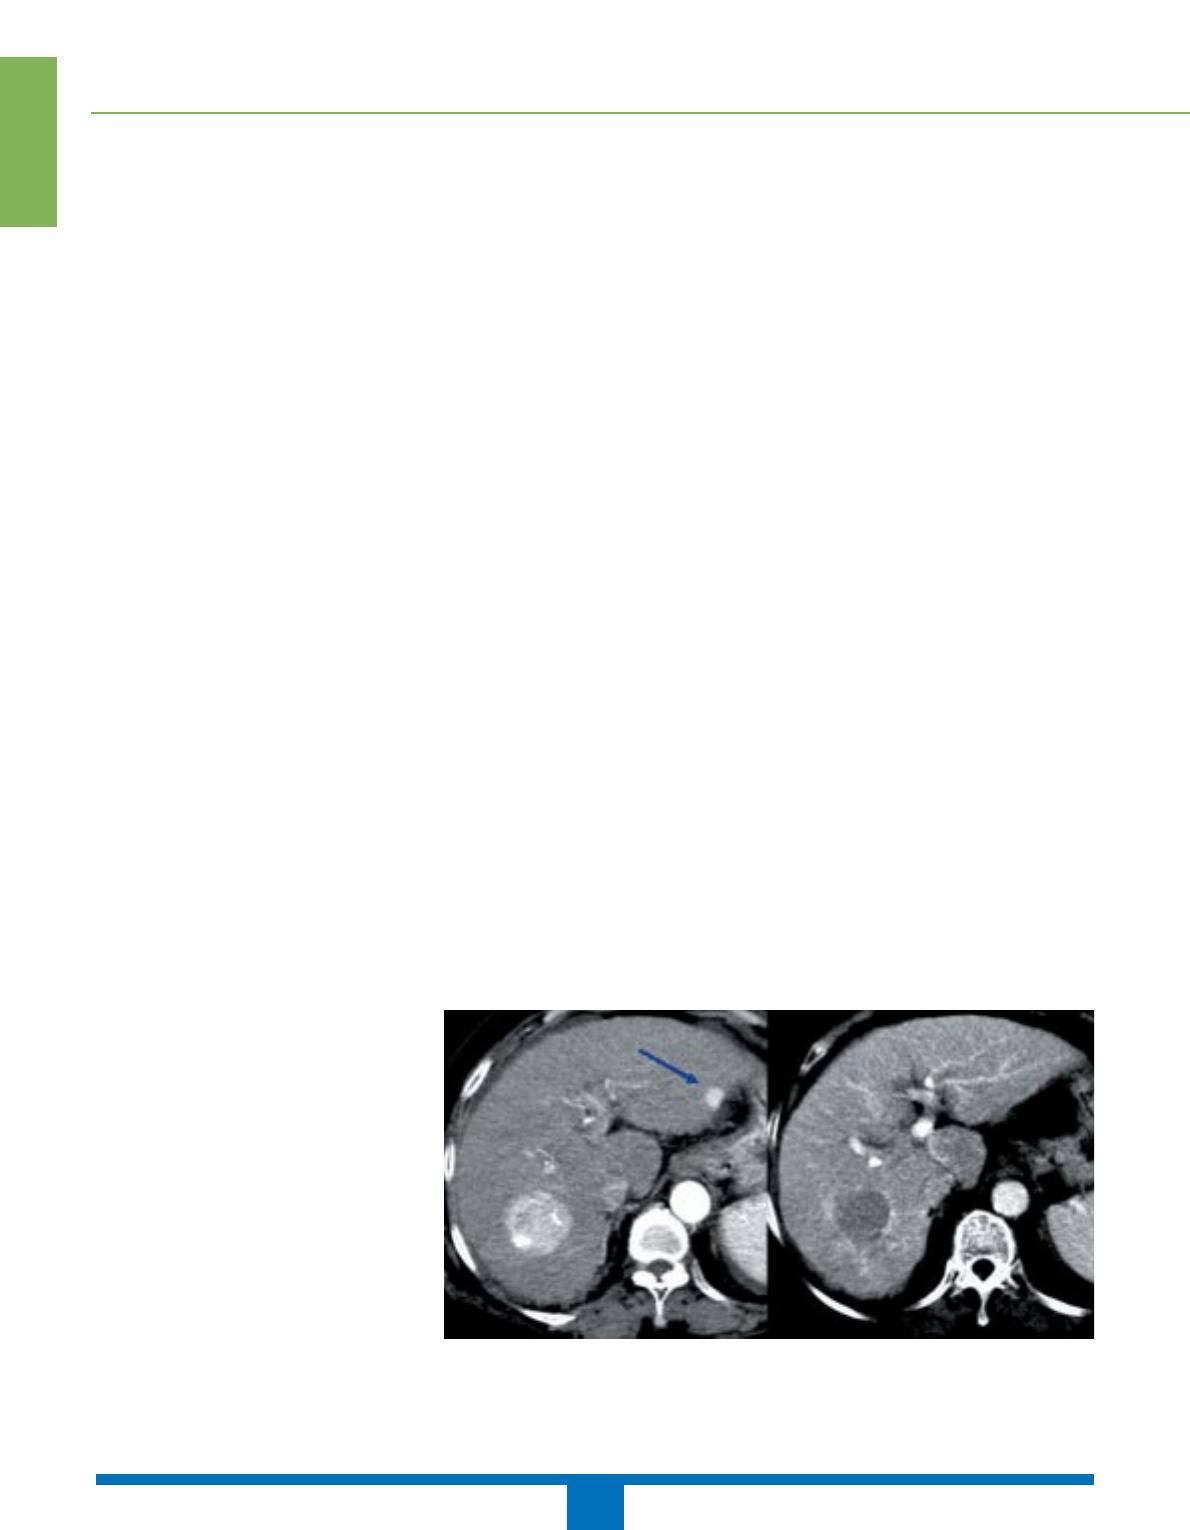

La présentation au scanner et à l’IRM

des hépatomes étant très variable, c’est

le caractère hypervasculaire d’une lésion

(figures 3, 4) suspecte qui constitue le

critère diagnostique le plus sensible et le

plus spécifique de CHC (16, 17). En

l’absence d’injection, le signal à l’IRM

des hépatomes, des macronodules de

régénération et des nodules frontières

chez un patient cirrhotique est trop

variable pour être considéré comme un

critère sémiologique fiable (16).

Figure 3 A et B. Carcinome hépatocellulaire. Mise en évidence de deux nodules hypervascu-

laires au temps artériel A. Le temps portal B. montre le retour rapide à l’hypodensité du nodule

hépatique droit, alors que le nodule hépatique gauche, bien visible au temps artériel (flèche),

n’est plus détecté.

AB

À l’heure actuelle, il est admis que le

scanner est une technique performante

pour détecter les hépatomes. L’étude de

Valls portant sur 85 CHC évalue la sen-

sibilité globale de cette technique

d’imagerie à 78,8 %, avec une élévation

à 93,6 % pour les lésions de plus de

2cm (17). L’IRM reste cependant dans

la littérature l’examen de référence pour

cette indication avec une sensibilité

encore supérieure (16, 18).

Figure 4 A, B et C. Carcinome hépatocellulaire : nodule hypo-intense en T1 avant injection A,hyperintense hétérogène au temps artériel B,

avec une prise de contraste périphérique au temps tardif traduisant la présence d’une capsule péritumorale caractéristique C.